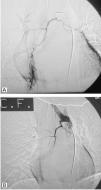

Caso clínicoNiña de 11 años que presenta emisión de sangre roja brillante por la boca, 3-4 episodios de 50ml/24h, sin antecedentes de infecciones respiratorias recurrentes ni traumatismos. Peso: 40kg (P50-75); talla: 143,5cm (P50); frecuencia cardíaca: 120 lpm; frecuencia respiratoria: 20rpm; presión arterial: 125/72 mmHg. Buen estado general. Hemodinamia, normal. Auscultación cardiopulmonar, abdomen y orofaringe, normales. Las analíticas seriadas al inicio, las 24, las 48 y las 72h posteriores fueron respectivamente: hemoglobina 13,4-12,7-11,9 y 9,3g/dl, y hematocrito de 38-37,4-34,6 y 27,3%. Las pruebas de coagulación fueron normales. La Rx de tórax al ingreso no presentó hallazgos patológicos. La fibrorrinolaringoscopia, la gastroscopia y el ecocardiograma, sin alteraciones. Evolución: en las primeras 48h persistió la hemoptisis. La angio-TC pulmonar (figs. 1–3) evidenció un tronco común con hipertrofia de arteria bronquial derecha originada en el arco aórtico adyacente en el origen de la subclavia derecha aberrante e imagen alveolar en base derecha. Se realizó una embolización endovascular selectiva (fig. 4) y una fibrobroncoscopia en el mismo acto. Se cateterizó, a través de vía femoral, la arteria bronquial de origen anómalo con hipervascularización patológica de lóbulo inferior derecho. Se utilizaron microesferas de 500-700μm en el procedimiento de embolización, con resultado satisfactorio.

En nuestra paciente, el hemograma seriado durante 48h objetivó descenso de 3g/dl de hemoglobina, sin alteraciones en las pruebas de coagulación, y la paciente permaneció hemodinámicamente estable. La angio-TC identificó la arteria bronquial derecha hipertrofiada con origen anómalo en el arco aórtico adyacente a subclavia derecha aberrante (fig. 2).